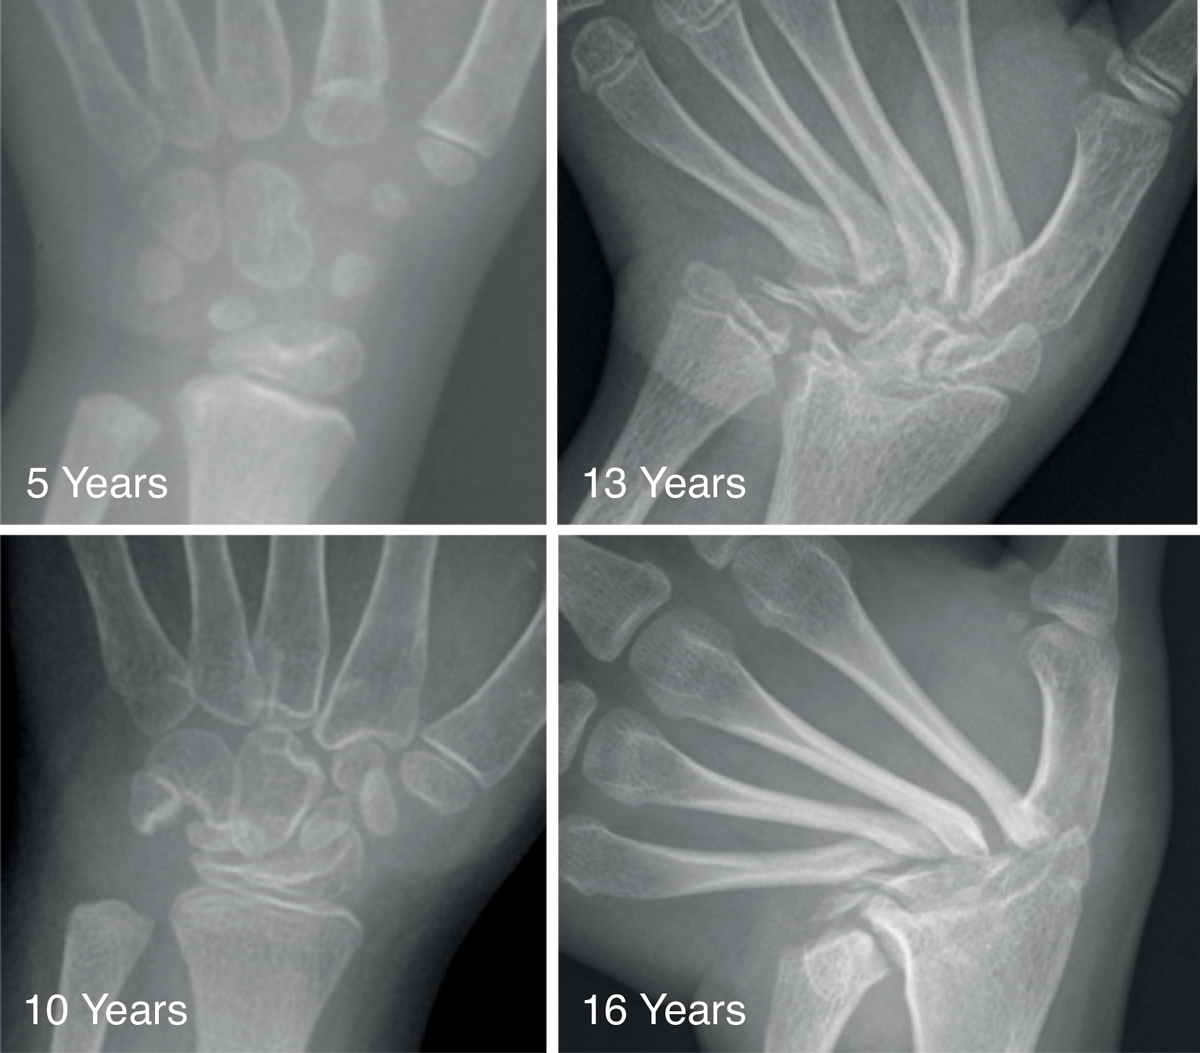

The course of the carpal bone destruction is presented in fig. 1. At the age of 5, the index patient possessed all carpal bones, but some alterations in location and orientation were evident. At the age of 10, the carpal bones showed erosions and partial destruction. At 13 years, the carpal bones and the epiphyses of the ulna and radius were almost completely resorbed. At 16 years, the proximal ends of the metacarpals showed progressive thinning and sclerosis, with ulnar deviation in the left hand. The tarsal bones revealed multilocular erosions at the age of 9 years. In contrast to the carpal bones, they did not become resorbed, but the erosions led to osteoarthritis (not shown).

Figure 1 Phenotype of the patient. X-ray images of the hands were taken approximately every 4 years. At the age of 5 years, all carpal bones were present but thereafter, they were gradually resorbed and were completely lost at about 16 years of age. Note that most of the other bones are intact. Only the metacarpal bones are affected at regions where they touch the carpal bones.